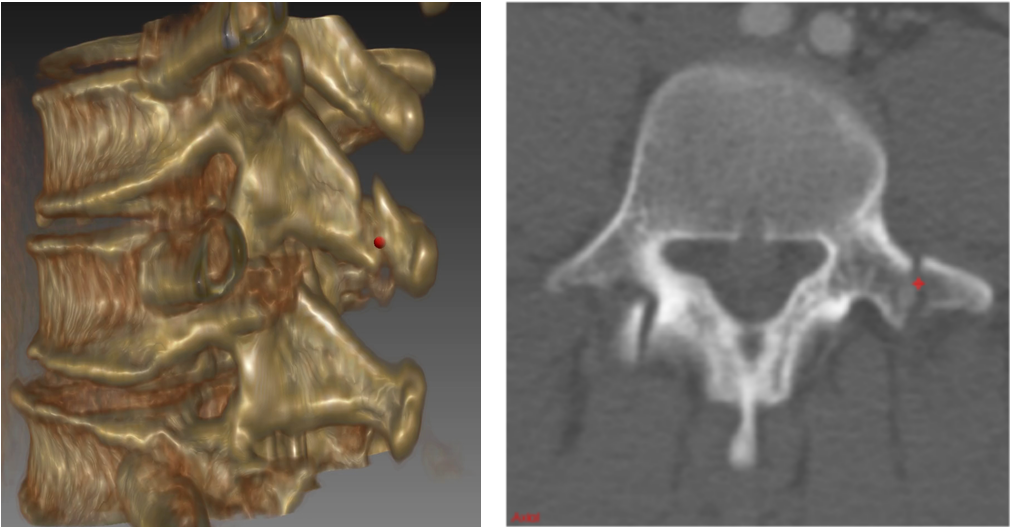

Injuries of the spine and its posterior elements in particular (see Figure 1) are a common occurrence in traumatic patients, with potentially devastating consequences [1]. Spine fractures are detected using volumetric imaging such as computed tomography (CT) in order to access the degree of injury. Spine injuries are a critical concern in blunt trauma, particularly in cases of motor vehicle collision and fall from significant heights. More than 140,000 vertebral fractures occur in the U.S. each year [2]. However, the traditional method of qualitative visual assessment of images for diagnosis could miss fractures, and is time-consuming, potentially causing delays in time-critical situations such as the treatment of spine injuries. Computer-aided detection (CADe) has the potential to expedite the assessment of trauma cases, reduce the chance of misclassification of fractures of the spine, and decrease inter-observer variability. Furthermore, CADe could help assess the stability and chronicity of fractures, as well as facilitate research into optimization of treatment paradigms.

In this work, we apply ConvNets for the automated detection of posterior element fractures of the spine. First, the vertebra bodies of the spine with its posterior elements are segmented in spine CT using multi-atlas label fusion [10, 11]. A set of atlases of the vertebra bodies are registered to the target image with free-form deformation. Then, an edge map of the posterior elements is computed using the Sobel operators

in order to find the horizontal () and vertical () approximations of the image derivative for each CT slice. Here, denotes a convolutional operation. Edge points are located at the maximum of the absolute gradient . The edge maps serve as candidate regions for predicting a set of probabilities for fractures along an image edge using ConvNets. An example of posterior-element segmentation and edge map estimation is shown in Fig. 3.

![]() |